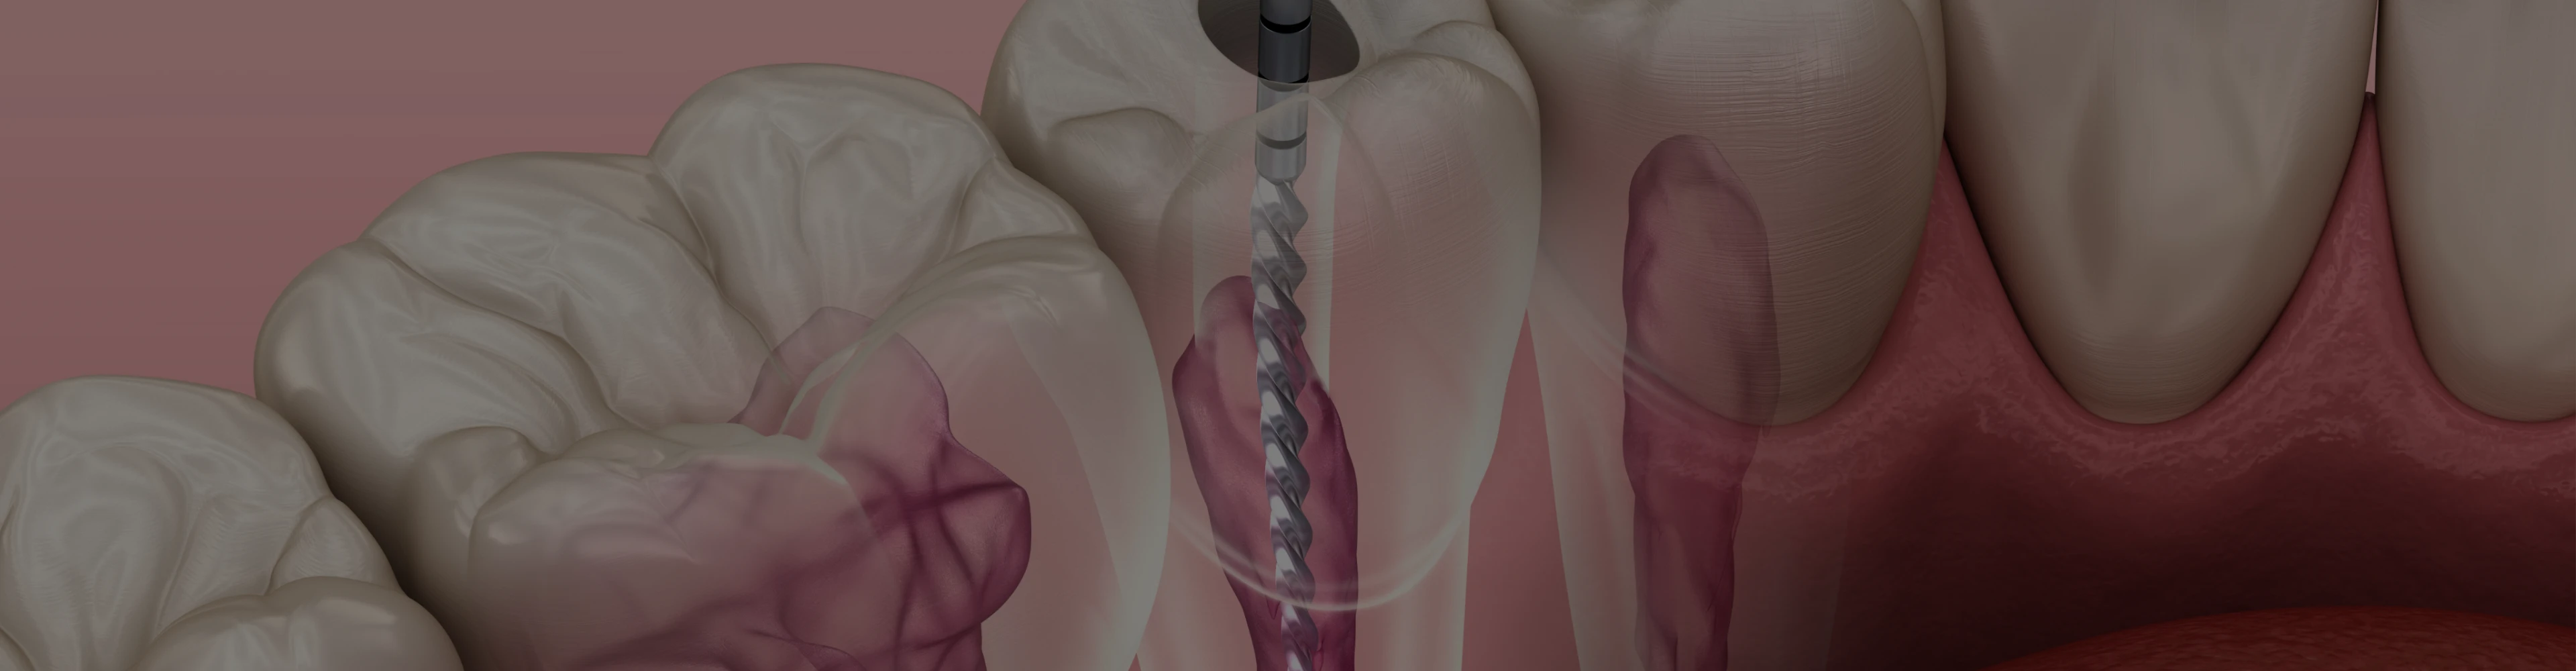

Endodontic treatment follows several key stages:

- Pulp access: Under local anaesthetic to ensure total comfort and absence of pain during treatment, an opening is made in the tooth to access the infected pulp.

- Cleaning the infected area: Infected tissue is removed, and the root canal is disinfected.

- Sealing the canal : Once clean, the canal is sealed to prevent reinfection.

The endodontic microscope is a tool used to improve the precision of root canal treatments. It enlarges hard-to-reach areas, facilitating the treatment of complex root canals.